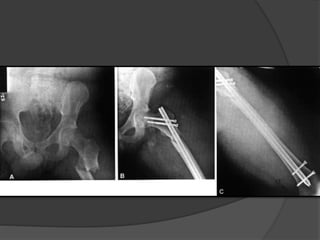

 Existen dos tipos de implante para estabilizar las fracturas

subtrocantéreas de fémur: (1) dispositivos de placa y

tornillo que se usan mediante reducción abierta y fijación

interna, y (2) clavos intramedulares aplicados mediante

técnicas abiertas o cerradas mínimamente invasivas

Tratamiento  Existendos tipos de implante para estabilizar las fracturas subtrocantéreas de fémur: (1) dispositivos de placa y tornillo que se usan mediante reducción abierta y fijación interna, y (2) clavos intramedulares aplicados mediante técnicas abiertas o cerradas mínimamente invasivas